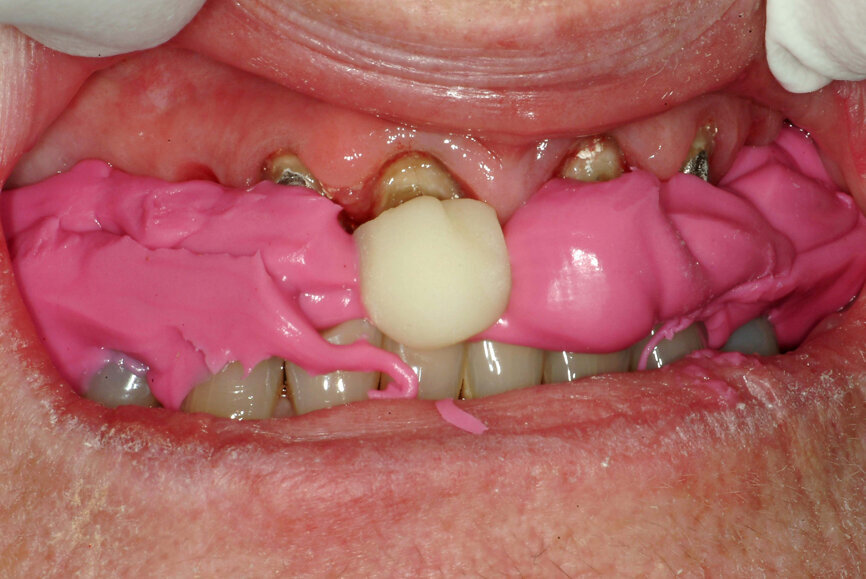

- Create a composite resin device (stop) on an anterior tooth (Fig. 21) at an approximate VDO to allow restorative space.

- Ask the patient to move the mandible forward and backwards two to three times. That will relax the lateral pterygoid muscles and allow the elevator muscles to position the condyles in a physiological position on the eminences.

- Adjust the composite resin device, using articulating paper, for a smooth mandibular movement. Also, adjust the height until the desired VDO is reached—evaluate the anterior space first, then the posterior space and then adjust the prepared teeth if needed to gain the appropriate restorative space.

- After the adjustments, ask the patient to maintain the backward position. That can be considered CR.

The technique for recording the CR position can be performed using analogue (Figs. 22 & 23) or digital methods (Figs. 24–27).